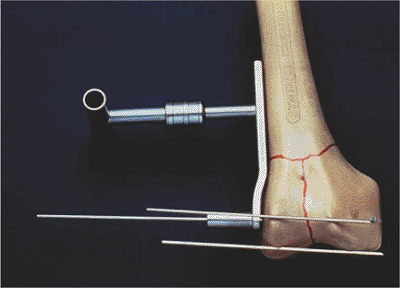

![]() |

|

Figure 45.6.

The 95-degree guide is placed on the lateral distal femur with one pin placed in front of the condyles and one pin placed at the distal tips of the condyles. This indicates the correct guide pin direction in two planes. |

Figure 45.7.

The anterior pin indicates the orientation of the trochlear notch. Central guide pin and screw placement should parallel this pin. |